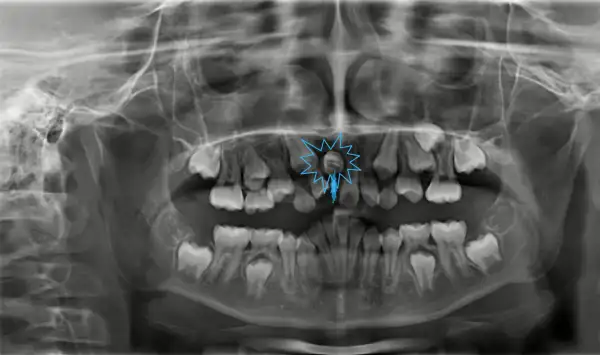

Răng Số Mấy Là Răng Nào?

Hàm răng của con người được đánh số hoặc phân loại theo vị trí và chức năng. Thông thường, răng được chia thành các nhóm chính như răng cửa, răng nanh, răng cối nhỏ và răng cối lớn. Răng số 8 là răng khôn. Việc xác định chính xác răng vĩnh viễn là răng nào và số thứ tự của chúng giúp ta hiểu rõ hơn về cấu trúc hàm răng.